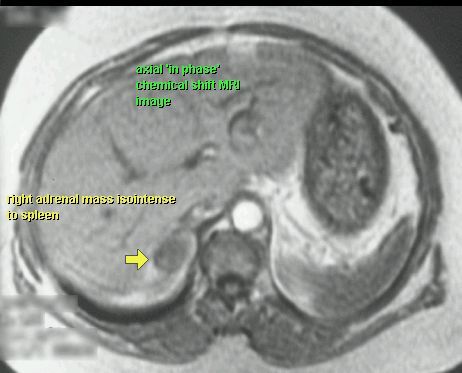

GRUCZOLAK NADNERCZA

MR